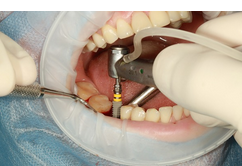

- 임플란트 삽입: 치과 의사는 임플란트를 안정적으로 삽입하기 위해 잇몸을 절개하고, 임플란트를 치아 뼈에 삽입합니다. 수술 후에는 굳게 고여있는 결손을 채우기 위해 뼈 이식이 필요한 경우도 있습니다.

- 치아 뼈에 인공 재질 삽입: 먼저 치과 의사는 국소 마취를 사용하여 치아 뼈를 위한 구멍을 뚫고 인공 재질을 삽입합니다. 이 인공 재질은 일반적으로 티타늄으로 만들어집니다.